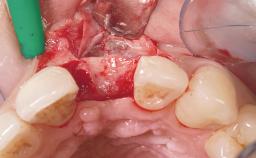

Late Placement of an Implant in a Maxillary Left Central Incisor Site

Bone Augmentation Horizontal|Staged

Augmentation Materials Xenogenous|Membrane

Soft Tissue Grafting Simultaneous